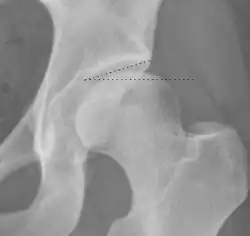

| Femoral head-neck offset | ![]() |

Offset of the femoral head with regard to most prominent aspect of the femora neck | >10 mm |